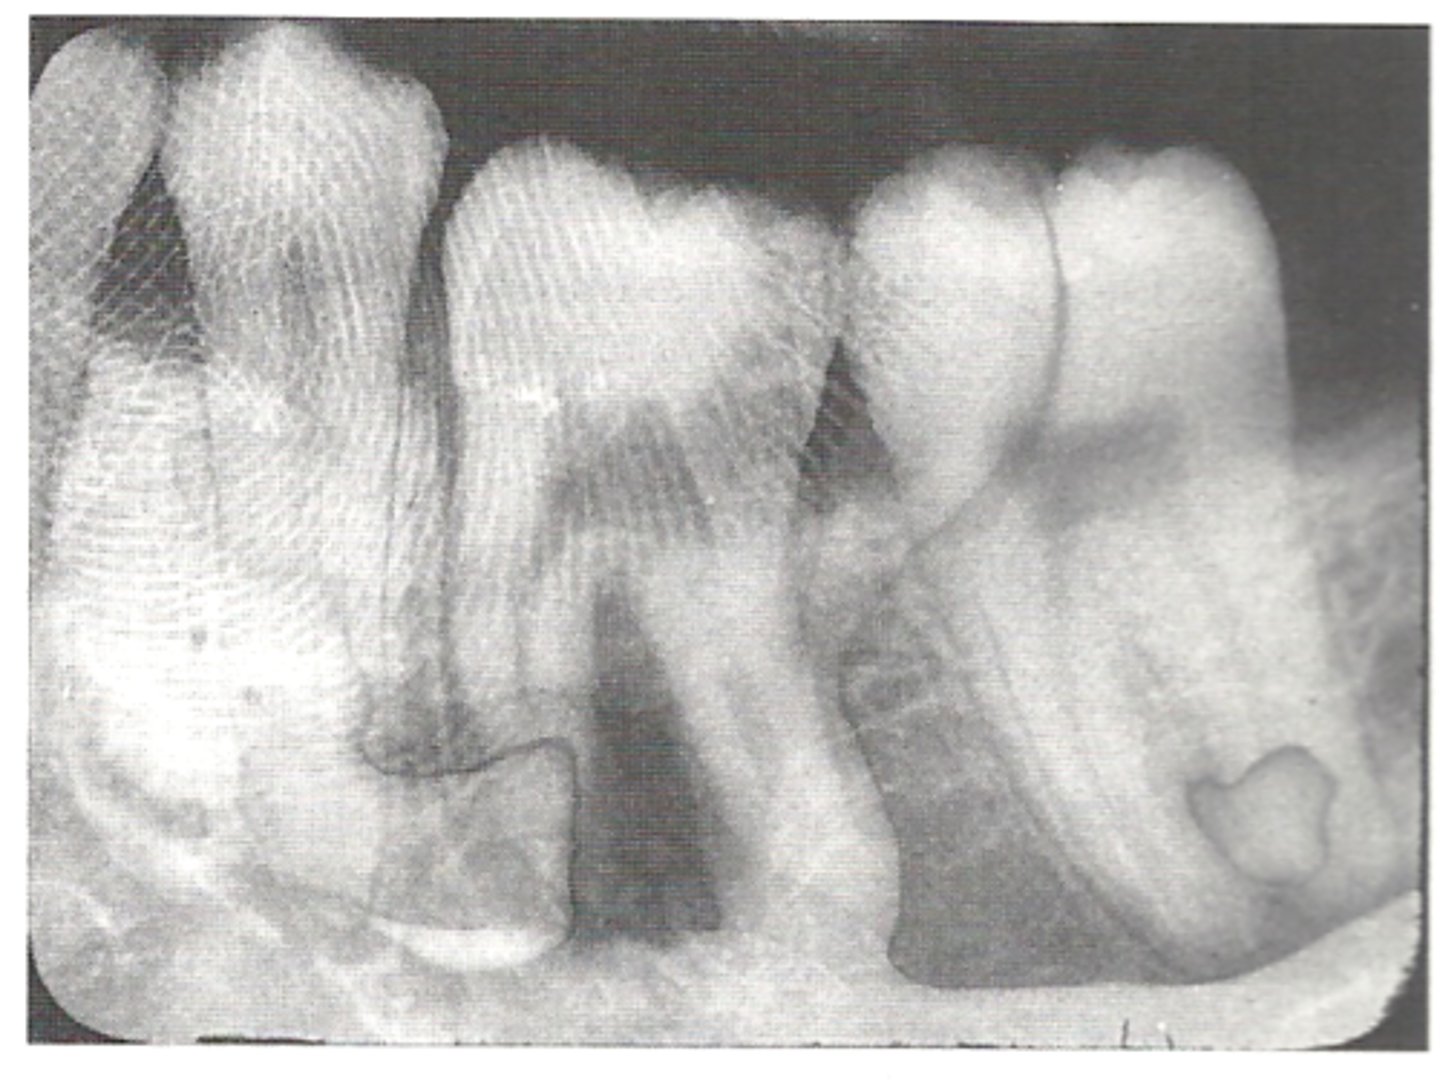

Phalangioma

Distal phalanx of the finger is seen in the radiograph

<p>Distal phalanx of the finger is seen in the radiograph</p>